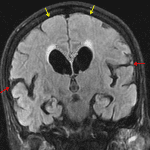

- Diffuse ventriculomegaly, particularly involving the lateral and third ventricles with subtle undulations along the margins of the lateral ventricles

- Disproportionate enlargement of the Sylvian fissures with mild crowding of sulci in the high paramedian frontal and parietal lobes

- Evans index = 0.35

- Callosal angle = 68 degrees

- Patchy T2/FLAIR hyperintensities in the subcortical and periventricular white matter

- Normal pressure hydrocephalus (NPH)

Diffuse ventriculomegaly, with configuration of the ventricles and extraaxial CSF spaces typical for normal pressure hydrocephalus (NPH).